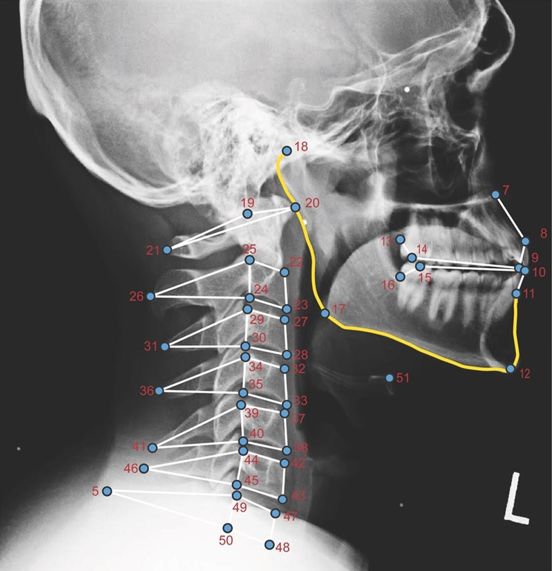

x线高清图谱 | 精致颞下颌关节解剖x线高清图谱 | 寰枢关节半脱位诊断

x线平片(许勒位,髁突经咽侧位及曲面体层):可发现有关节间隙改变和